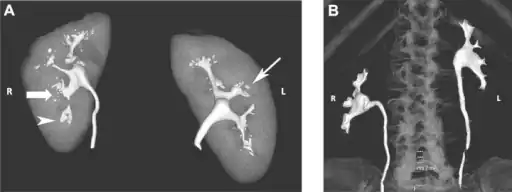

a)Bilateral papillary necrosis b)appearance of a normal papilla

Cystoscope